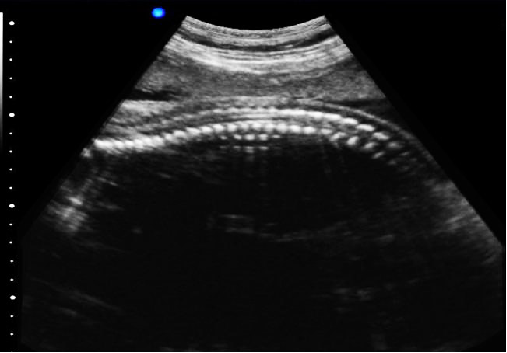

P5-VET手提式獸用彩超機(jī)心臟超聲檢查圖

心臟超聲檢查:

心臟超聲是唯一能動(dòng)態(tài)顯示心腔內(nèi)結(jié)構(gòu)、心臟的搏動(dòng)和血液流動(dòng)的儀器,對(duì)人體沒(méi)有任何損傷。心臟的各個(gè)結(jié)構(gòu)清晰地顯示在屏幕上。通過(guò)彩超的測(cè)量,醫(yī)生可了解瓣膜病變的程度以決定保守治療還是手術(shù)治療。心肌的增厚、心腔的擴(kuò)大都要依賴彩超來(lái)判斷;對(duì)冠心病,彩超能直觀顯示心肌的運(yùn)動(dòng)狀況及心功能,向臨床醫(yī)生提示心肌缺血的部位。